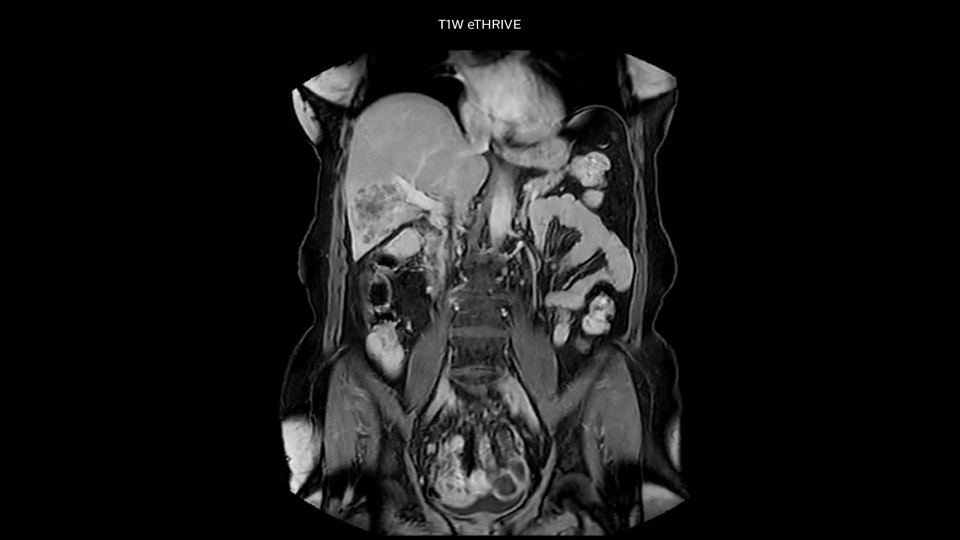

“Our liver exams are quite fast,” says Dr. Baumann. “If the patient tolerates it, we use an arms-up position to reduce the FOV and speed up the exam with dS SENSE.”

“We acquire one transversal high resolution T2-weighted sequence with 3 mm slice thickness, for example for pancreas or liver lesions. Then we also add a T2 fat suppressed MultiVane XD SPIR sequence. We perform these two routinely in our liver imaging. We use high dS SENSE factors to significantly shorten scan times to 2-4 minutes, which can improve our protocol; it’s a very robust scan.”

“We include mDIXON for the dynamic sequences because of the robust and homogeneous fat suppression we get with that. We had been using eTHRIVE, but we are now quite happy with mDIXON. Sometimes we use a medication to calm the bowels, to further improve the image quality.”